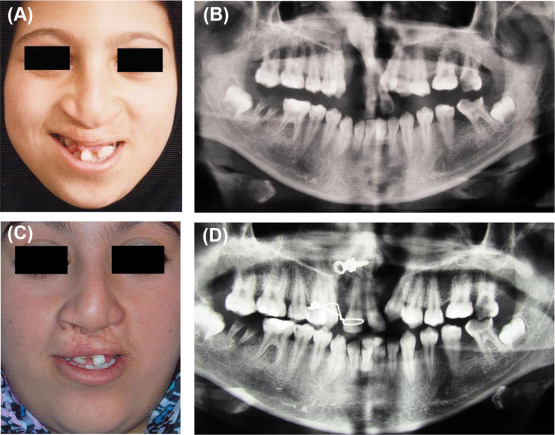

(A) Photograph taken during childhood shows protruded and twisted premaxilla. ...

Figure 5.

(A) Photograph taken during childhood shows protruded and twisted premaxilla. (B) Orthopantomograph (OPG) prior to the surgery. (C) Full-face photograph taken 3 months after the first surgery. Note the healed right lip scar and improvement in lip shape. The left side bone grafting was performed using the conventional method. (D) OPG taken 3 months after the premaxillary osteotomy and right side bone grafting.

This procedure was performed in three patients, with good labial repair after the lip split. The bone graft was successful in all cases, and there was no complication for premaxillary osteotomy in this series. The premaxilla was stable and firmly adhered to the lateral segments with bone (Figure 5).